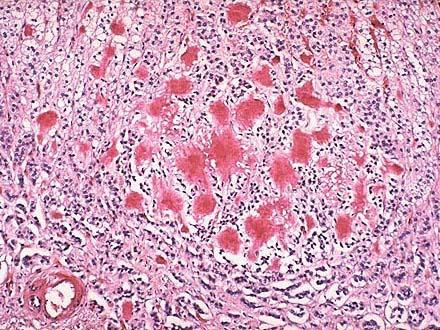

问题 患者,27岁,男性,两年来出现渐进性无力,低血糖,低血钠,低血压及色素沉着等症状。B超示双侧肾上腺肿大。行手术治疗,术后病检镜下见皮质细胞萎缩,皮质窦隙内大量匀质无结构物质沉积,刚果红染色如图所示,正确的诊断应是 ( )

选项 A.肾上腺淀粉样变 B.肾上腺纤维化 C.肾上腺坏死 D.肾上腺出血 E.肾上腺炎

答案 A